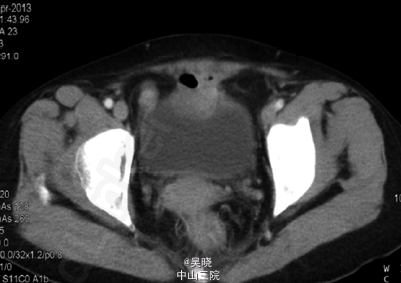

查体:未见明显异常。 相关肿瘤标记物未见明显异常。 上腹部增强CT 示肝脏多发小囊肿、右下肺多发结节。 下腹部增强CT于膀胱前方可见软组织肿块影,直径约3.7cm,其与膀胱、部分肠腔及前腹壁分界不清,增强可见强化。